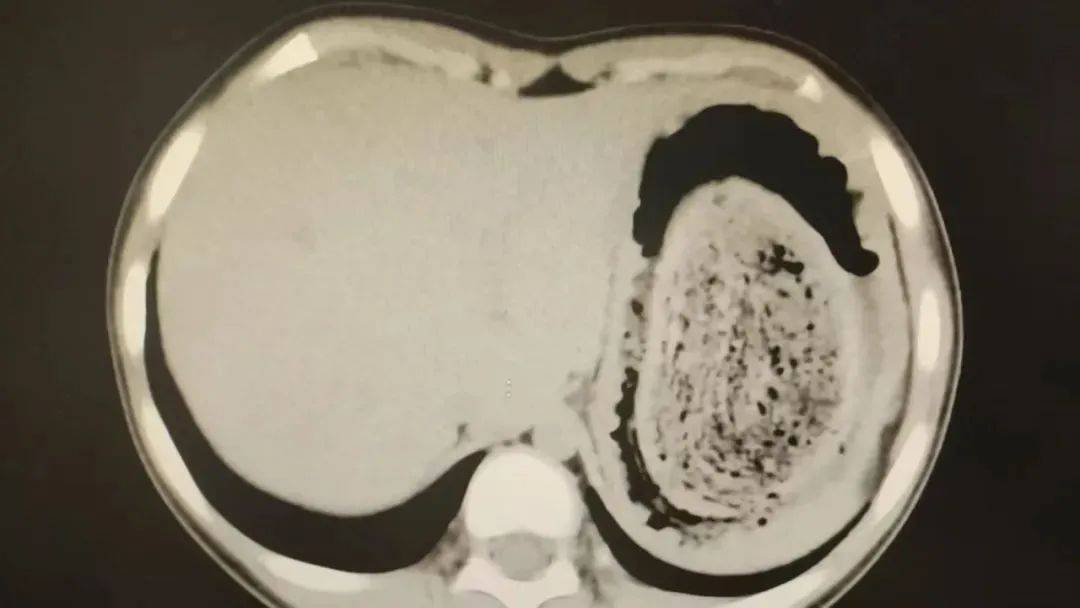

在胃镜帮助下,妮妮胃里的情况逐渐明了皇冠登3管理出租 。一个滚圆黑色的毛发球混合着食物残渣占据整个胃腔,这些头发相互缠绕形成一个实心的“发石”,此外胃里还有一个鸡蛋大小的溃疡。

症结找到了,就是这个巨大的发石导致妮妮出现营养不良、贫血和闭经,当务之急就是取出“发石”,给胃进行“大扫除”皇冠登3管理出租 。

头发缠绕在一起十分坚硬,体积巨大,胃镜尝试多次均难以取出,医护人员不得不采取开放手术的方式来取“发石”皇冠登3管理出租 。

7月14日,武汉儿童医院肝胆肿瘤外科副主任医师朱真闯主刀皇冠登3管理出租 。术中见妮妮胃部足有正常状态2倍大,切开胃壁后,一股酸臭味弥漫开来。

“发石”混杂着食物残渣,就像一个黑色的小西瓜皇冠登3管理出租 。由于整个“发石”体积太大,为避免损伤胃壁,医生借助手术工具将“发石”切割、分解,再小心翼翼地分块取出。整场手术持续2个多小时,最终取出4斤头发碎片。

10岁女孩园园(化名)因持续3天的上腹痛伴呕吐被紧急送医皇冠登3管理出租 。影像学检查结果显示,她的胃部存在一个巨大的团块状阴影,初步怀疑为异物堵塞。据家长回忆,园园从1年前开始就有偷偷吃头发的习惯,但家人并未重视,直到这次症状严重才意识到问题的严重性。